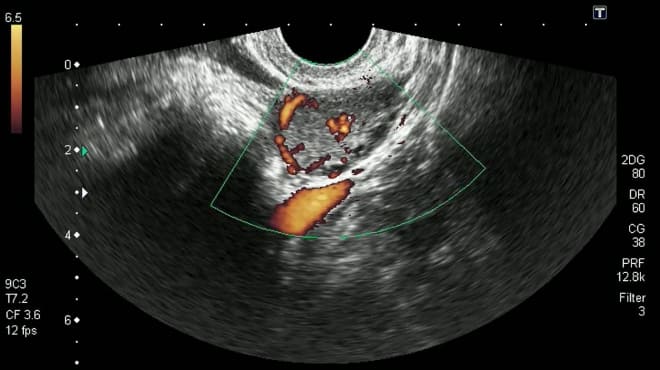

| Наличие кровотока в образовании | Визуализация кровотока внутри образования с помощью допплерографии. | Подтверждает наличие активного жёлтого тела. Отсутствие кровотока может указывать на регресс жёлтого тела или другие патологии. |

На УЗИ желтое тело выглядит как округлая или овальная структура с характерной эхогенностью, что позволяет отличить его от других образований в яичниках. Важно отметить, что наличие желтого тела не всегда указывает на беременность; его можно обнаружить и в циклах, когда зачатие не произошло. Однако, если желтое тело визуализируется на ранних сроках беременности, это может служить подтверждением нормального протекания беременности и функционирования яичников.